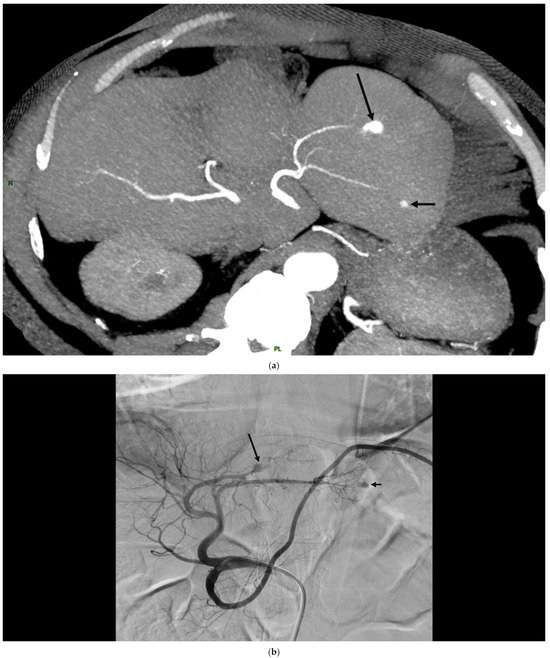

- Boukobza, M.; Ilic-Habensus, E.; Arregle, F.; Habib, G.; Duval, X.; Laissy, J.P. Hepatic artery aneurysms in infective endocarditis: Report of 10 cases and literature review. Ann. Vasc. Surg. 2024, 105, 252–264. [Google Scholar] [CrossRef]